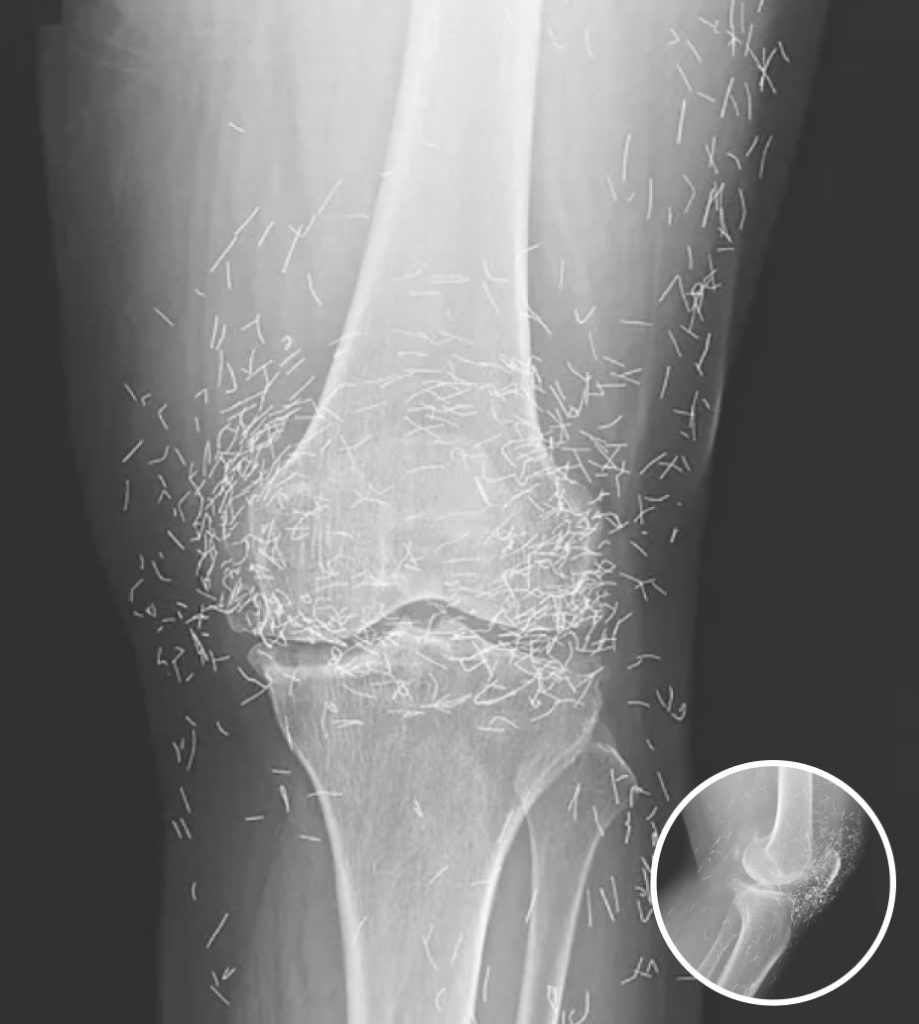

A routine X-ray revealed an unexpected surprise when doctors examined the knees of a 65-year-old woman suffering from severe joint pain. What they found was nothing short of astonishing — hundreds of tiny gold needles embedded deep in her tissue.

Acupuncture, a traditional therapy widely used in Asia, involves inserting thin needles into specific points on the body in an effort to relieve pain or treat illness. In this case, however, doctors say the gold needles were left behind intentionally as part of her treatment plan, designed to deliver continuous stimulation to the affected area.

There are other complications as well. Needles lodged in tissue can interfere with medical imaging. “They can obscure parts of the anatomy on an X-ray,” Guermazi noted. Even more alarming, patients with metal fragments in their bodies should never undergo an MRI, as the magnetic force could cause the needles to move — potentially puncturing blood vessels and causing life-threatening damage.

As for the South Korean woman, her case was recently documented in the New England Journal of Medicine. While the needles may have been intended to help, her X-rays tell a cautionary tale about the potential risks of extreme alternative therapies.